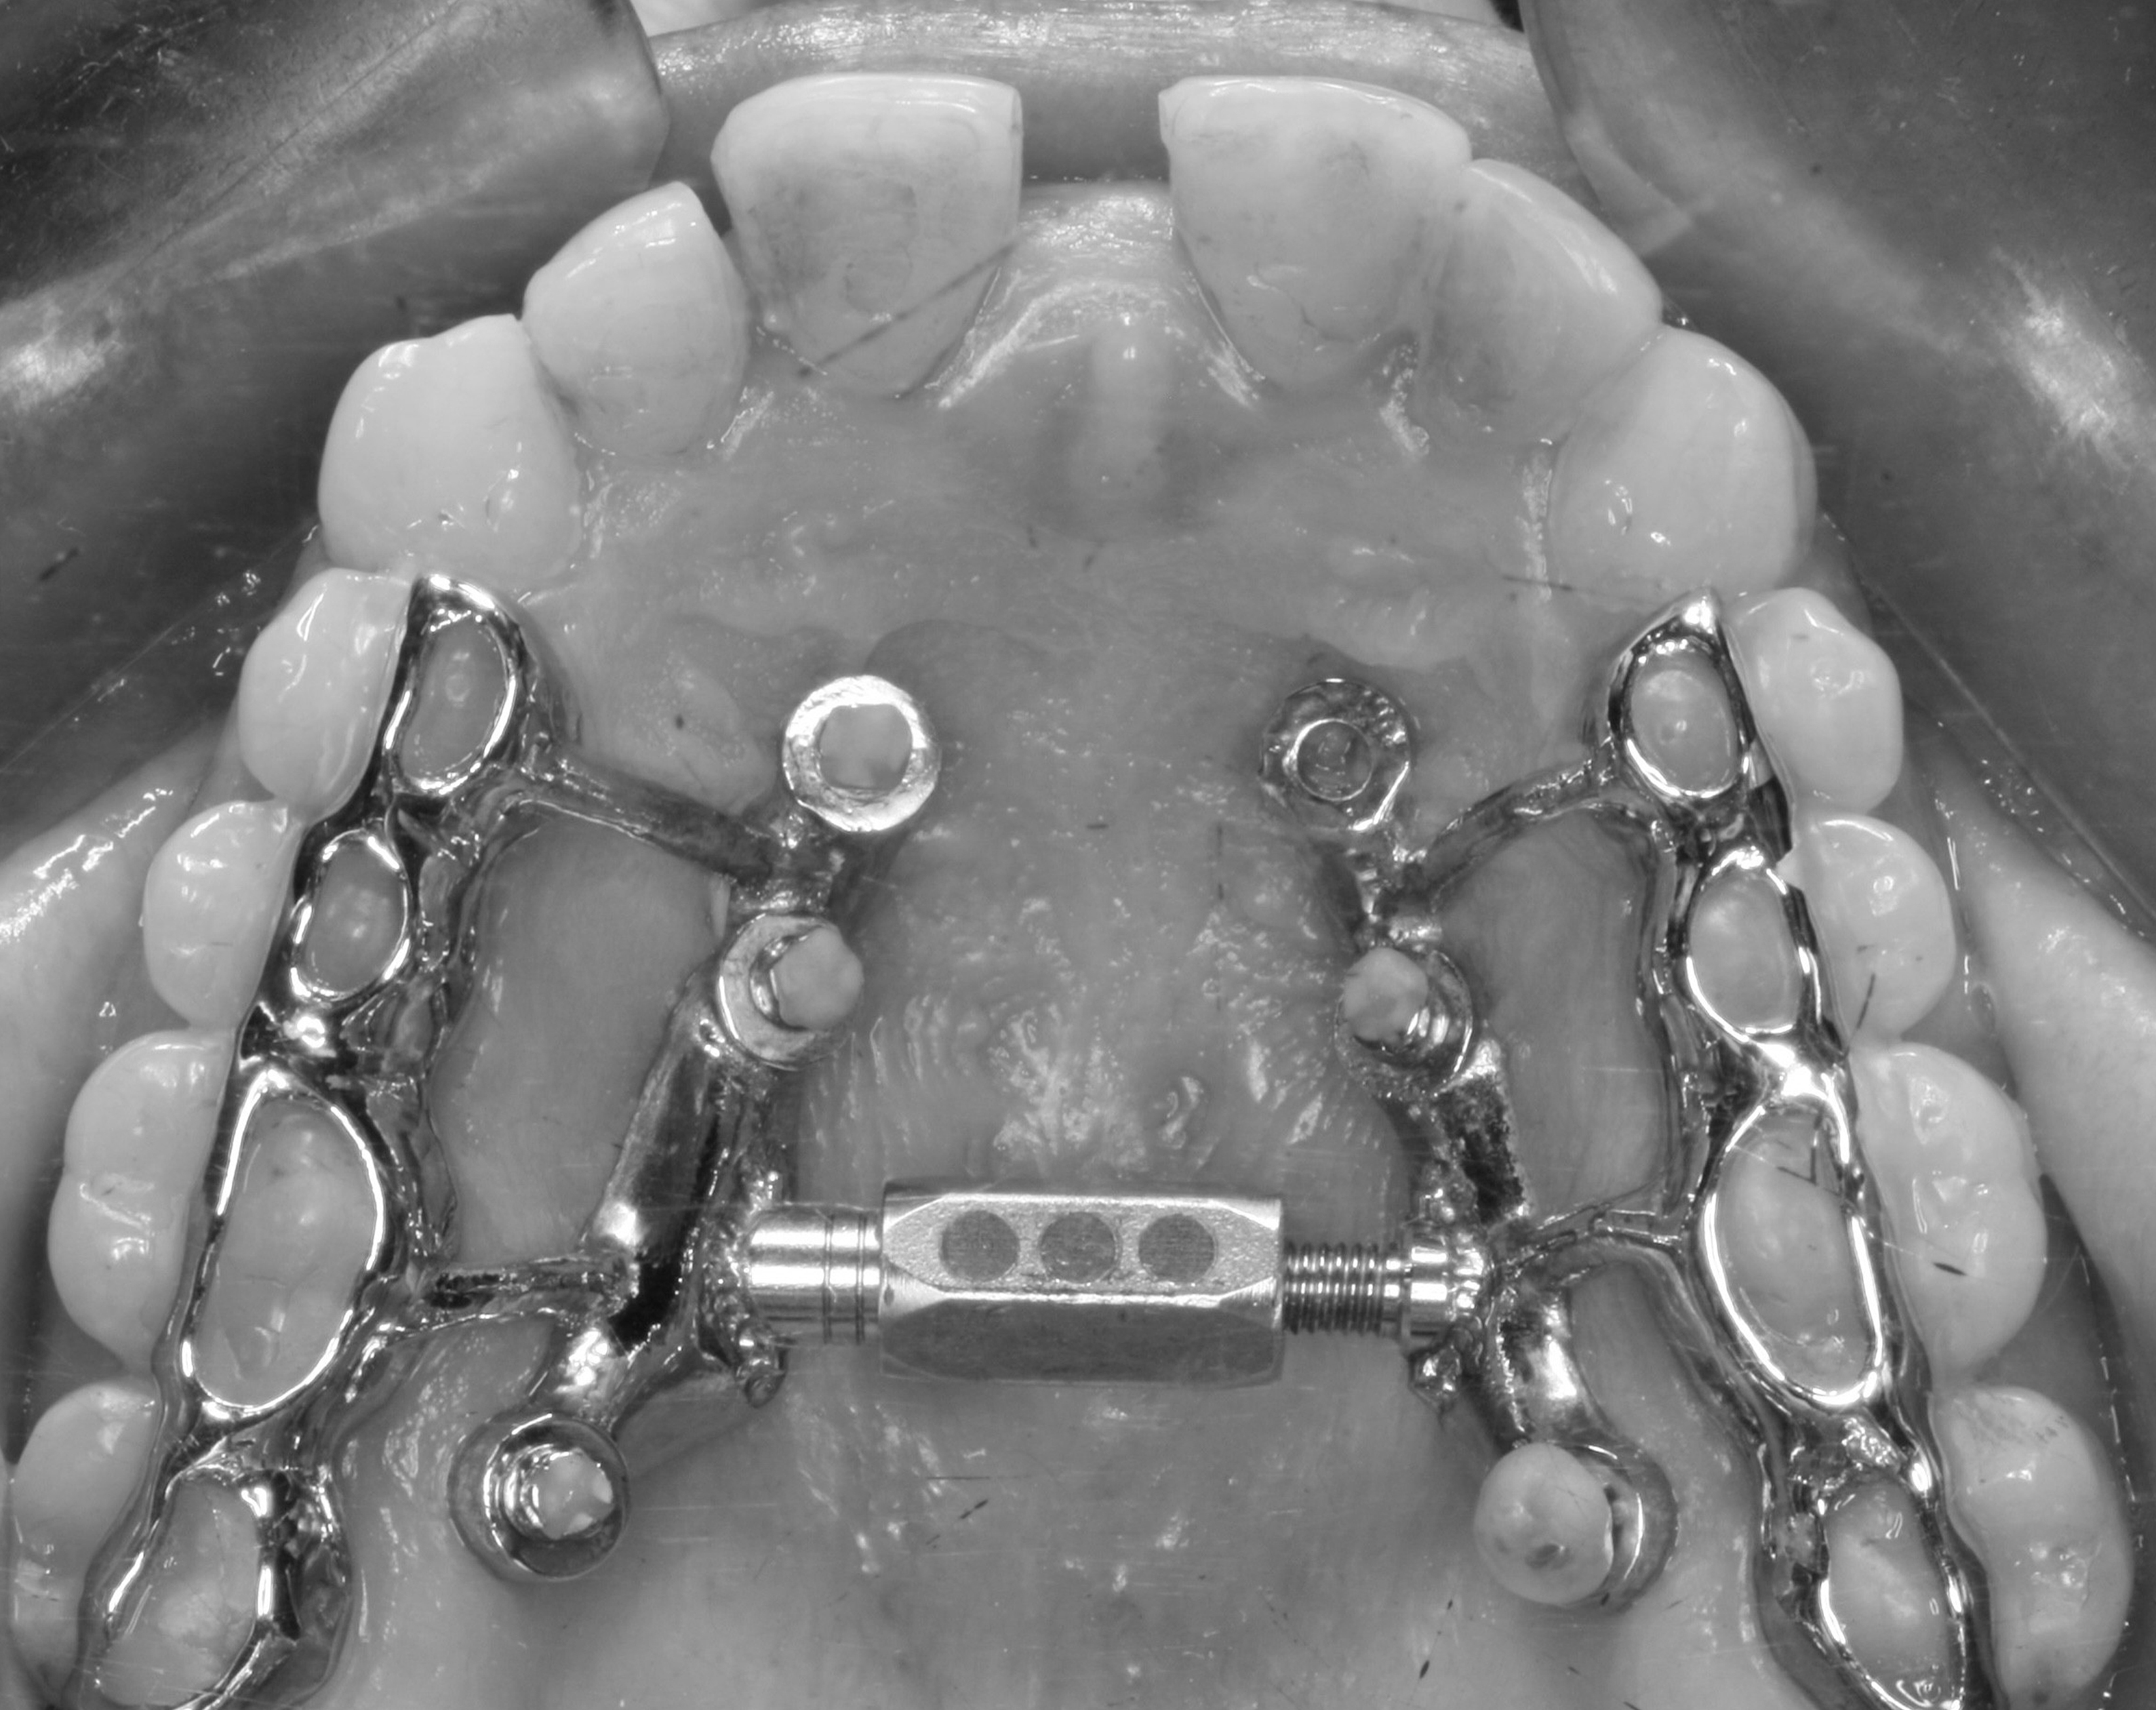

Anclaje esquelético MARPE guiado.

3. XCROSS/EXPANSIÓN: La tercera llave es la integración. Cuando biomecánica, cirugía y tecnología se alinean, los límites desaparecen, se amplian las fronteras. Ni la edad ni la complejidad son barreras cuando hay protocolo guiado. Lo que antes era imposible, hoy se resuelve con confianza.

MAPE en adultos y MISMARPE.

Clínico e investigador nos abrirá las puertas del MAPE en adultos con y sin asistencia quirúrgica con protocolos basados en la eficiencia clínica sin complicaciones.